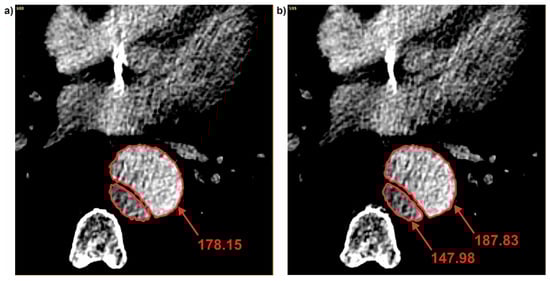

3.2. Brightness Value Analysis

| Patient | Average Brightness | ||

|---|---|---|---|

| Common | True | False | |

| Pat I | 184.73 ± 16.75 | 141.36 ± 20.26 | 178.01 ± 6.04 |

| Pat II | 331.11 ± 18.41 | 364.03 ± 14.10 | 320.10 ± 12.60 |

| Pat III | 291.13 ± 6.60 | 213.52 ± 39.70 | 313.91 ± 8.62 |